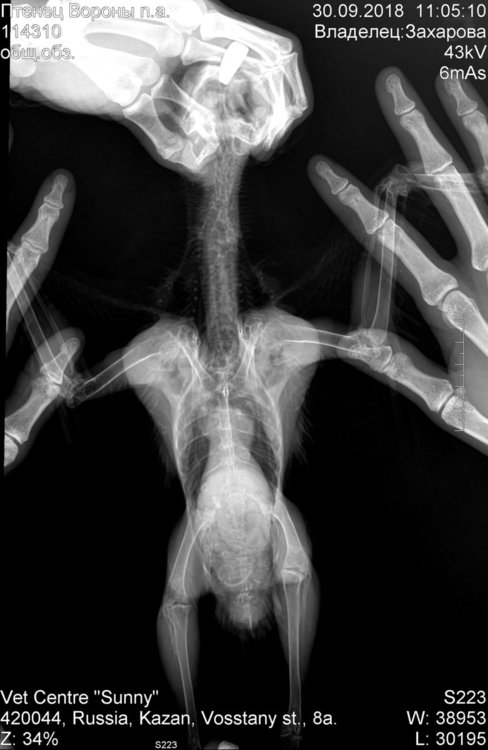

Dzakharova Опубликовано 1 октября, 2018 Автор #61 Опубликовано 1 октября, 2018 Добрый вечер! Не стала создавать отдельную тему, продолжу здесь. Вчера были у ветеринара, в связи с тем, что несколько недель был плохой стул. Сделали анализ на лейкоцитоз, взяди мазок из зева, посмотрели помет, сделали снимок. Как ьказалось, помет это можно сказать единственное что нормально, лейкоциты паравда тоже не повышены, мазок тоже без особенностей. Снимки прилагаю, также расшифровку ветеринара: По рентгену печень увеличена и рентгеноконтрастность повышена, воздухоносные мешки с затемнениями (птица не может летать, поэтому грибковое поражение очень может быть). Поэтому от глист обязательно птицу обработать, добавить в рацион насекомых, иммунофан, если можете, также продолжайте хотя бы месяц. Также я рекомендую на 2мес'продолжить кетаконазол по предыдущим назначениям, гептрал или гептор ( или же гепатовет) начинать давать. Вопрос, насколько все плохо? И мое традиционное - страдает ли птица? По состоянию он довольно крепкий, по крайней мере при всяческих манипуляциях очень бойко отбивается, аппетит хороший, активность у него стандартно не очень высокая.